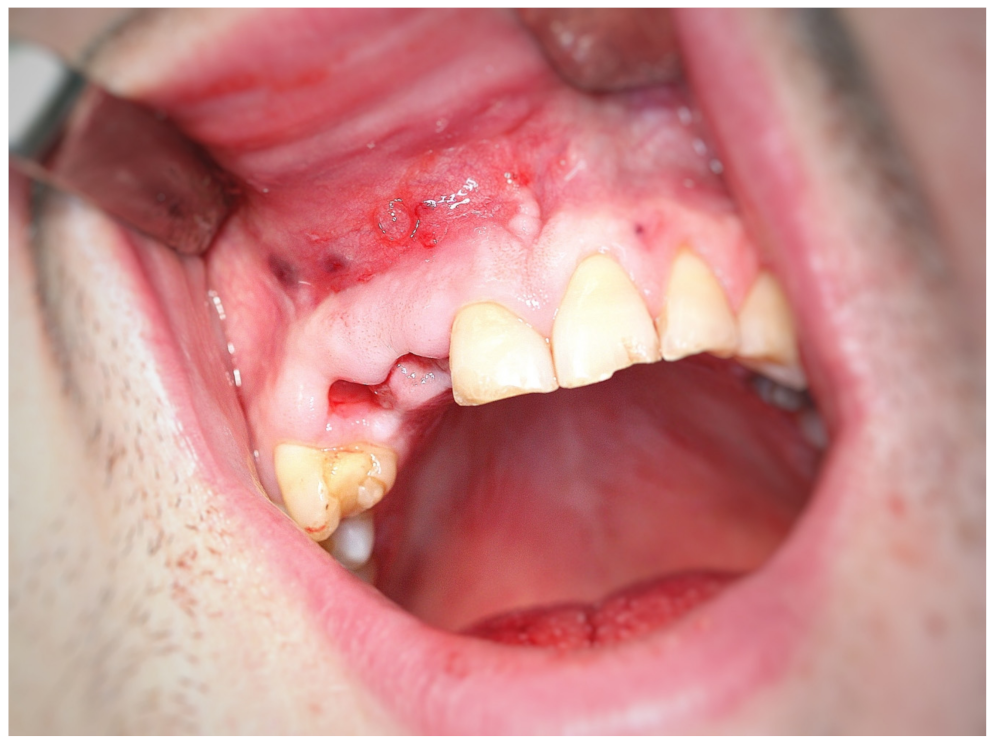

3.2. Surgery